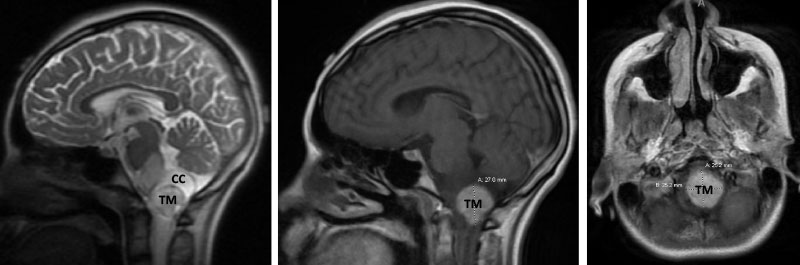

Following, the intramedullary brainstem tumor was successfully resected via suboccipital craniotomy and upper cervical laminectomy. The patient did well after surgery.

Figure 3. Immediate post-op CT (left) and two-year follow-up MRI (right).